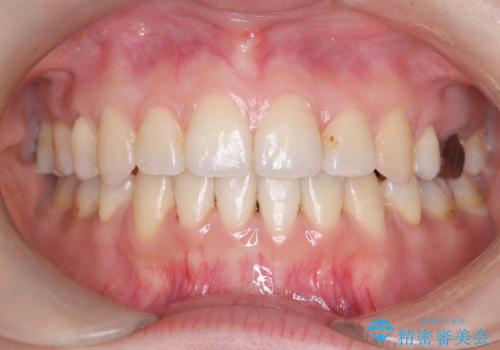

【ワイヤー矯正】口元を下げたい、下の歯の凹凸を無くしたい

- 主訴:口元を下げて前突感を無くしたい、下の歯の凹凸も無くしたい

右側第二小臼歯、左側第一小臼歯、下顎両側第一大臼歯を抜歯しワイヤ-矯正を行いました。

骨格的顎の変位を認めたため、顔貌に対しピッタリ上下の歯の正中を合わせることは難しいと説明し、上下左右計4本小臼歯を抜歯しワイヤー矯正治療を行いました。